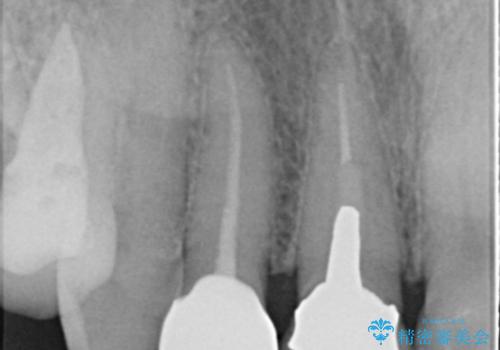

- 右上2番の審美性改善を主訴に来院された患者様です。

切削量と前歯ということからオールセラミッククラウンでの治療を選択しました。